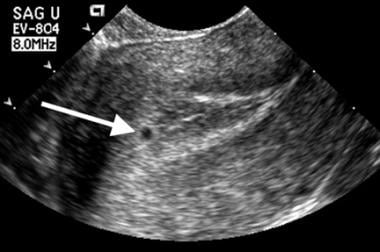

The gestational sac forms early in pregnancy to enclose an embryo and amniotic fluid. Certain sac characteristics can indicate a compromised pregnancy.

First-Trimester Ultrasound: Early Pregnancy Failure - First-Trimester Ultrasound: A Comprehensive Guide

Early Pregnancy Loss (Embryonic Demise) Imaging: Practice Essentials, Ultrasonography

Early pregnancy ultrasound explained : GS , YS and FP